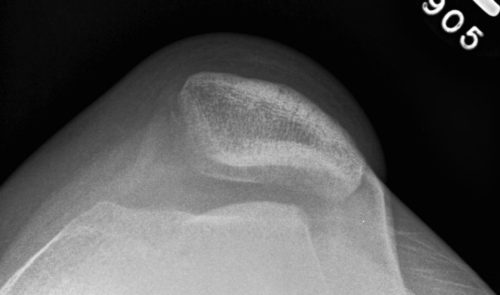

Patellar (patellofemoral) instability surgery